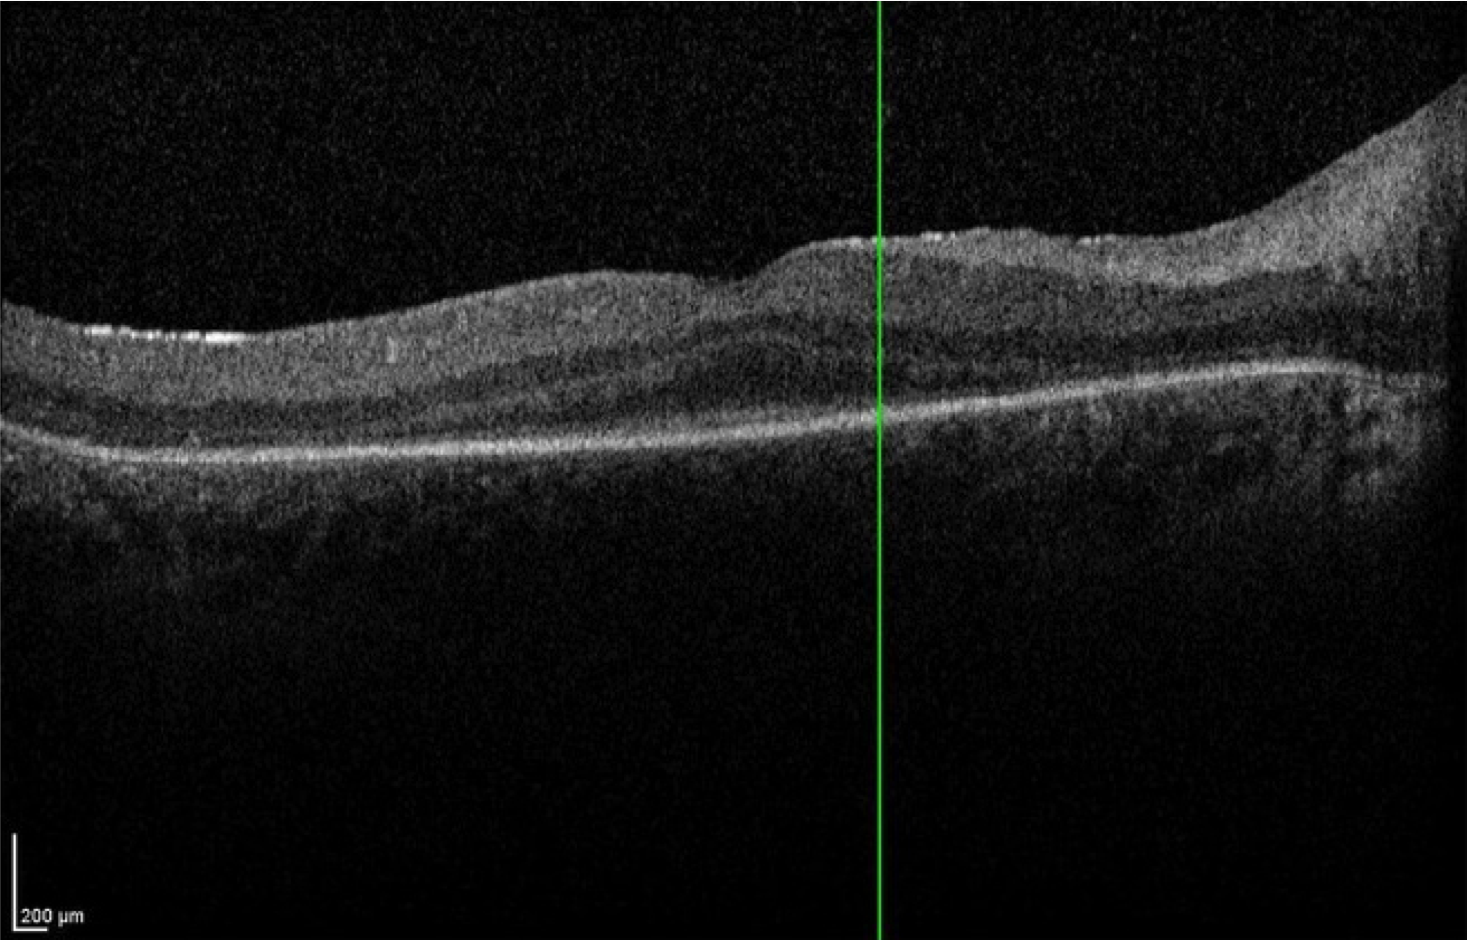

Case 13 is a 15 year old male was noted to have abnormal vision at 3 months of age. He had large amplitude nystagmus, did not respond to his parents faces and would not follow any type of toy or light that was put in front of him. His pupils constricted when the room lights were turned off and dilated when they were turned on. Retinoscopy revealed over seven diopters of hyperopia and electroretinography detected no responses under any stimulus conditions. The best acuity ever recorded has been bare light perception. His parents have normal vision.

Optical coherence tomogram of the right eye.